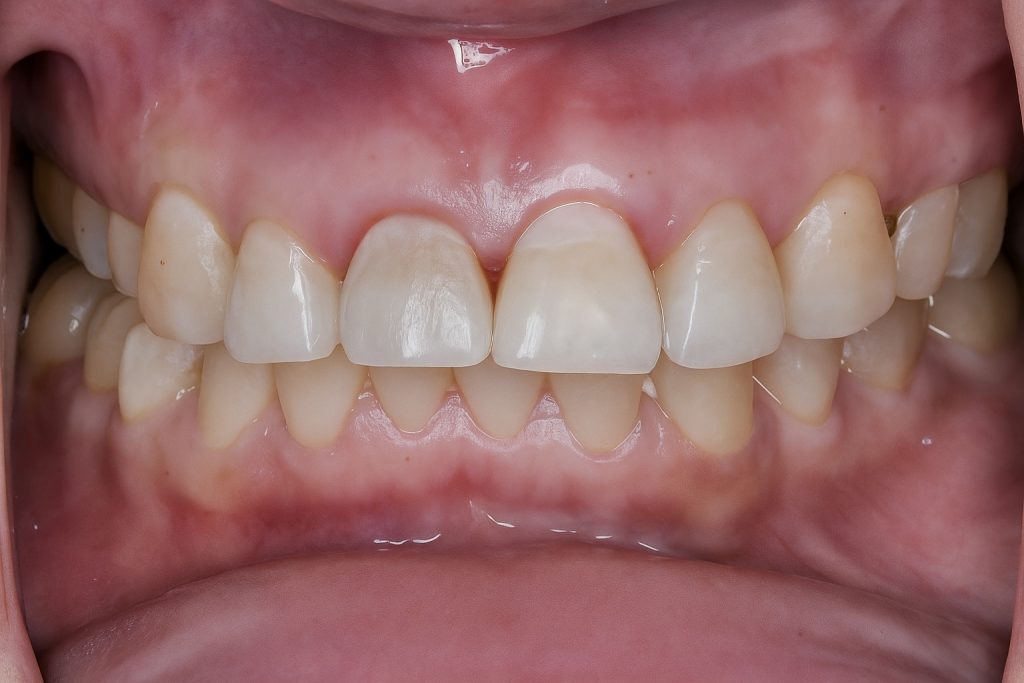

Full isolation was achieved using a pink rubber dam and clamps #1A and 2A for cross-arch stabilization (Fig 3–4).

Deep dentin zones were rebuilt using GC EverX Posterior (fiber-reinforced dentin replacement) for internal toughness and crack resistance, followed by Tokuyama Estelite Sigma Quick for enamel layering (Fig 9–10).

Morphology and surface texture were sculpted under microscope vision to achieve natural light diffusion and line-angle harmony.

Final finishing was completed with Lucida polishing system + PoGo points, achieving high gloss and enamel translucency continuity.

Post-operative X-ray confirmed ideal apical and coronal seals (Fig 11).